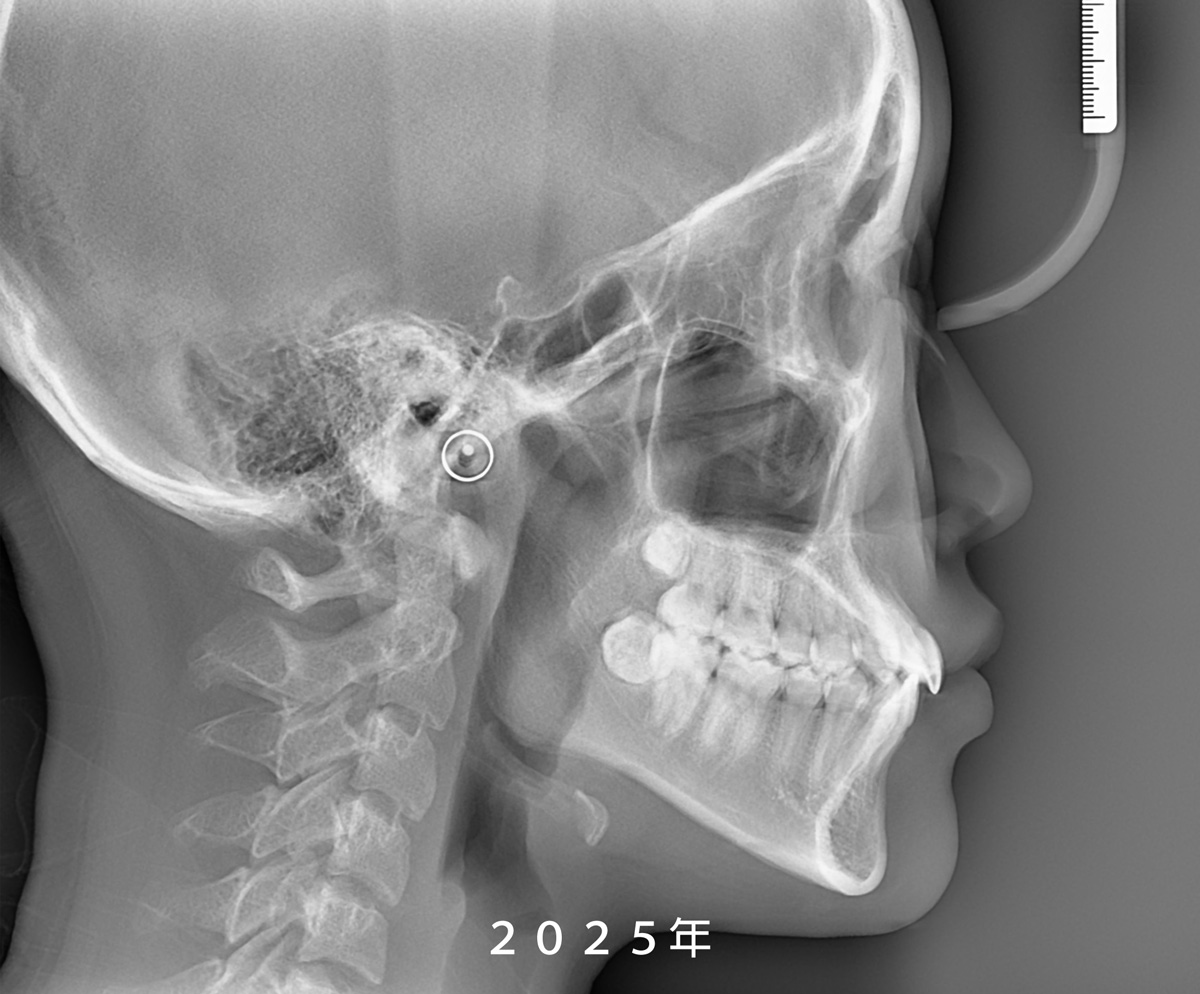

從 X 光片重疊影像可以發現,

她的鼻子與下巴都有明顯的成長變化,

但所幸前牙並未發展成

我們較為擔心的反咬(negative overjet)問題。

Because the pandemic reduced Yun’s visit frequency for nearly two years, it unexpectedly gave us a clearer window into her jaw growth. Superimposed X-rays showed noticeable changes in both her nose and chin, but thankfully her front teeth never shifted into a negative overjet, which is a common concern in skeletal Class III cases.

對於骨性三級(下顎較前突)的孩子來說,下顎持續生長時,上排門牙常會自然地略微外傾,藉此覆蓋下排牙齒,這是一種身體自行調整的「牙齒補償」。在不動手術、僅以矯正治療的情況下,醫師必須持續觀察門牙的角度,避免過度外翻。幸好,小妘的門牙角度始終維持在自然範圍內,微笑時齒切面完整、微笑曲線柔和,看起來自然又美觀。

As the lower jaw grows, upper incisors often tip forward slightly as a natural form of compensation to maintain overlap. When treating without surgery, it’s crucial to monitor this angle to prevent excessive flaring. Fortunately, Guanyun’s incisors stayed within a healthy range, giving her a smooth smile arc and a naturally balanced look.